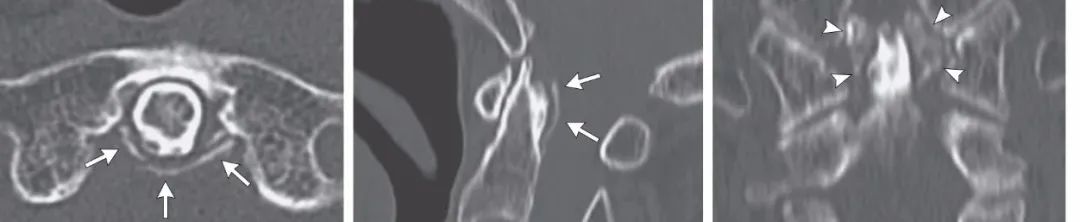

明确诊断主要通过影像学方法,颈椎CT是关键。 颈长肌钙化性肌腱炎特异性的影像表现是C1-4椎体前缘软组织肿胀和积液与C1椎体前弓下方不规则钙化沉着共存。

图:C1椎体前弓下方不规则钙化沉着

图:椎前积液

图:椎前积液和C1椎体前弓下方不规则钙化沉着

图:椎前软组织肿胀

CT的高分辨率能够明确肌腱内的钙化,能够明确是钙化而不是其他骨骼来源的高密度影。 钙化一般位于寰椎前弓的下方和枢椎齿状突的前方,少部分可位于下颈椎前侧 。CT有助于明确椎体前积液的存在和排除其他病理表现,如骨折或脓肿。MRI对诊断不是必须,但有时可帮助确定软组织异常,排除咽后脓肿,脊椎炎或肿瘤。 MRI检查T2加权在椎前可见局限性的裂隙样区域,大多位于C1-4水平,呈高信号改变,这反应是由于炎症引起的积液 。T2加权、脂肪抑制序列和T1加权对鉴别积液和脂肪组织、含脂肪的骨髓以及咽后感染、脊椎炎有重要作用。MRI检查在钙化检查方面存在不足,T2加权呈低信号。